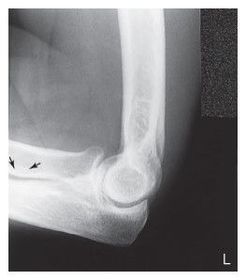

C. anterior fat pad D. posterior fat pad E. supinator fat stripe (not visible)

Which fat pad of the elbow will only appear on x-ray if there's a joint pathologic process? Posterior Fat Pad

Why does the elbow need to be in 90 degree flexion to determine whether the posterior fat pad is visible or not? When elbow is flexed more or less than 90 degrees it pushes the fat pad into different position, it can show up on x-ray then when there's no pathologic issue